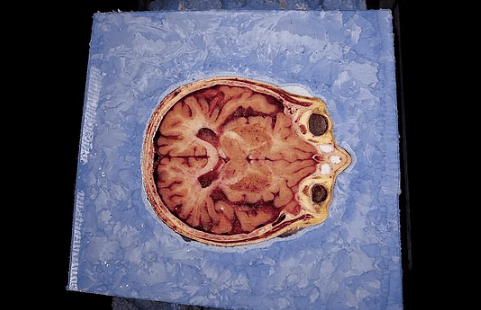

Sue bu ziyaretlerinde hem tıp öğrencileri ile tanışıyor hem de öldükten sonra vücudunun nasıl kesip fotoğraflanacağı hakkında daha detaylı bilgi alıyordu.